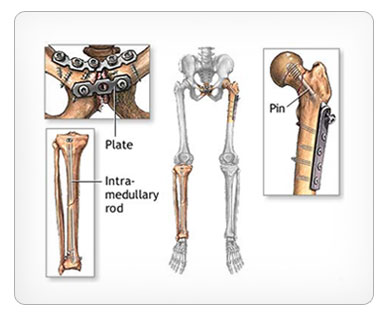

Many fractures require surgery to repair. Though surgery comes with its own risks, modern orthopedic techniques can lead to improved outcomes. The surgical technique used will depend on the nature of the specific fracture. Some of these techniques include:

» Metal plates may be screwed onto your broken bone to prevent it from moving and to promote healing

» Metal rod may be placed inside the center of a long bone to help reattach two ends of a fracture and to maintain alignment. This technique is called intramedullary fixation

» Pins and rods may be placed in your bones and continue outside your skin, where they can be attached to a metal cage. This technique is known as External fixation and allows for slight adjustments to be made to the orientation and position of a bone as it heals.